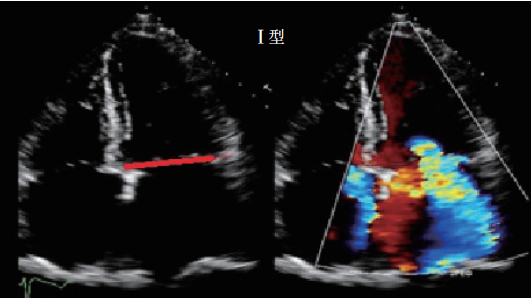

Ⅰ型:瓣叶活动正常而瓣膜功能失调(图2)。在Ⅰ型功能失调中,收缩期和舒张期瓣叶活动幅度正常,反流的原因为瓣叶穿孔或瓣叶对合不良导致(瓣环扩张)。

图 2 Ⅰ型,正常瓣膜运动